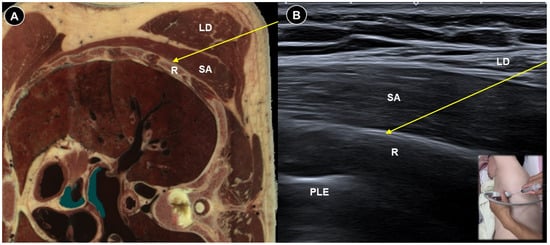

| Painful polyneuropathy | Numbness, tingling sensations, dysesthesia, weakness, balance impairment | Metabolic, infections, connective tissue disorders, hereditary, toxins, nerve injuries, etc. |

|

| Ultrasound facilitates targeting small distal nerves | |